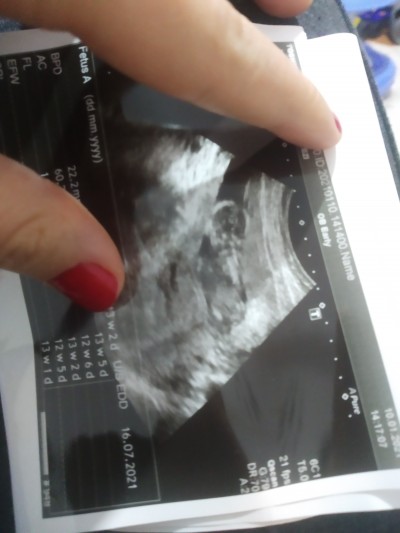

Merhabalar 13+3 günlük hamileyim suyum azmis bol su içeceğim hatta sandviç gibi sıkışmış bebek dedi bu durumu yaşayan varmı ne gibi sıkıntılar olabilir çok üzüldüm

image